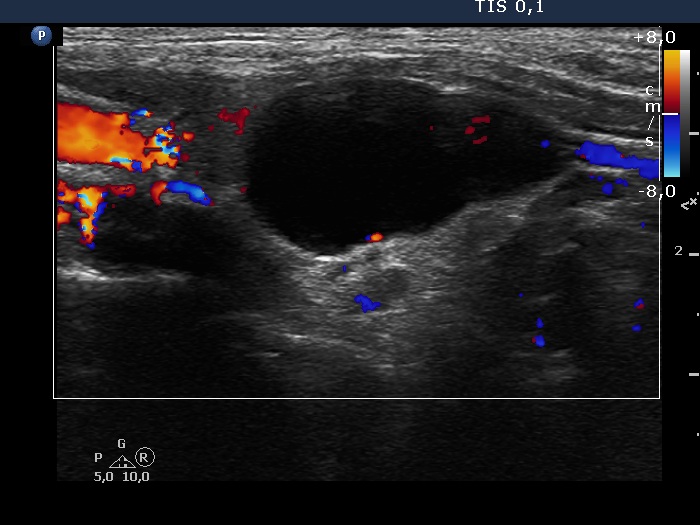

Ultrasonography. The thyroid was moderately hypoechoic and has several more hypoechoic areas corresponding to the underlying Hashimoto's thyroiditis. There was a cystic lesion under the lower pole of the right lobe. This was an almost complete cyst.

Additional tests: serum-parathormone 28.0 pg/mL (normal value 12-88), parathormone content of the aspirated fluid 302 pg/mL.